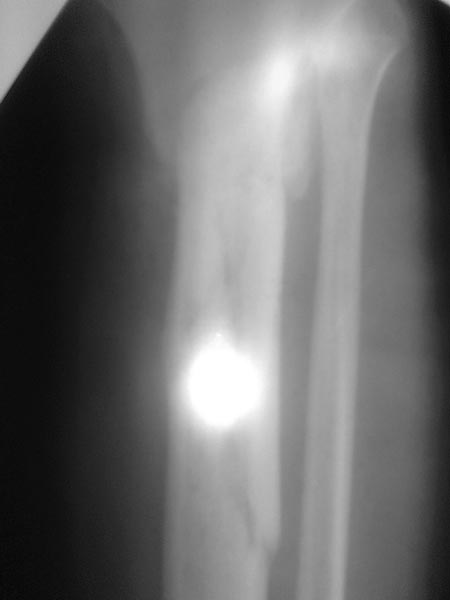

Важны мнения опытных докторов владеющих интрамедуллярным остеосинтезом. Пациент 50 лет.В анамнезе з/оскольч.перелом в/з-с/3 б/б кости. Был в АВФ 9 мес, демонтирован по его словам по поводу спицевой инфекции.также был со слов вскрыт гнойник на передней поверхности голени в зоне ложняка. на данный момент клинически: патол.подвижность в в/з голени и заживающая рана 0,2*4см по передней поверхности голени в зоне ложняка с скудно-умеренным серозным отделяемым( скорее вне зоны проведения спиц). Подвижность -умереннная. Трофических и сосудистых нарушений можно сказать нет. Сгибание в коленном суставе возможно без насилия ок. 50град. Вопрос - как делать? Нам предстваляется два пути: 1.Не дожидаясь заживления раны о/с АВФ,с открыванием ложняка: почистить его+ остеотомия малобрецовой ближе к н/3-с/3 границе. 2.перевязывать рану, после заживления подождать недельки две. Паралельно разрешить приступать на конечность. 2.1Если гной будет то см.вариант1.

2.2 Если гноя нет возможна ли установка штифта ???Т.к. 1) верхнее плечо перелома короткое 2) Риск сломать осколки при штифтовании в связи с разрушением эндостальной мозоли 3) угроза инфицирования, конечно если нагноится то опять см. вар.1. Есть конечно варианты штифта с антибиот покрытием, но это не панацея. У кого был такой опыт поделитесь пожалуйста наблюдениями( лучше с проиллюстрированными R)

Жаль, что нет фасной проекции. Перелом на 2 уровнях, есть искривление костно-мозгового канала. Проксимальный отломок короткий. Вывод: лучше не штифтовать.

3.Перелом на 2 уровнях, есть искривление костно-мозгового канала. Проксимальный отломок короткий.